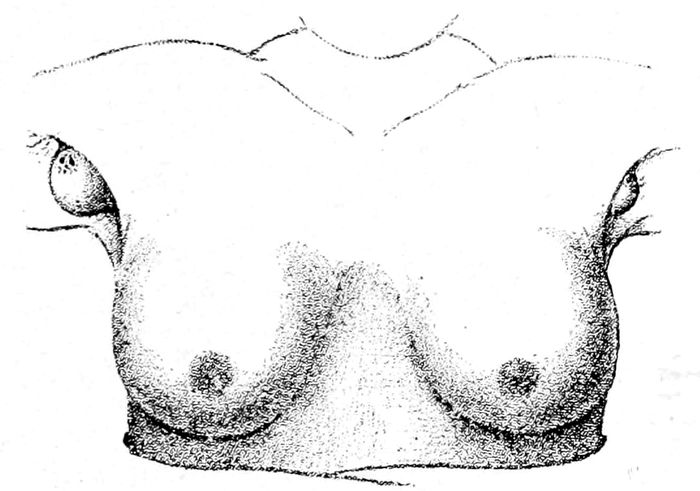

Fig. 10.—Supernumerary milk glands in the axillæ. They may be found also below the breasts. (Witkowski.)

Fig. 11.—The three ages of the breast—virginity, maturity, and senescence. (Witkowski.)

that more than two breasts may be found on the

human female, and not infrequently pieces of mammary

32tissue may be discovered in the axilla or on the chest or

back.

The mammary gland is undeveloped at birth, but, nevertheless

it may fill with milk (witches’ milk). At puberty,

after marriage, and during pregnancy, the gland

reaches maturity. It is only after delivery, however,

that the functional climax is attained.